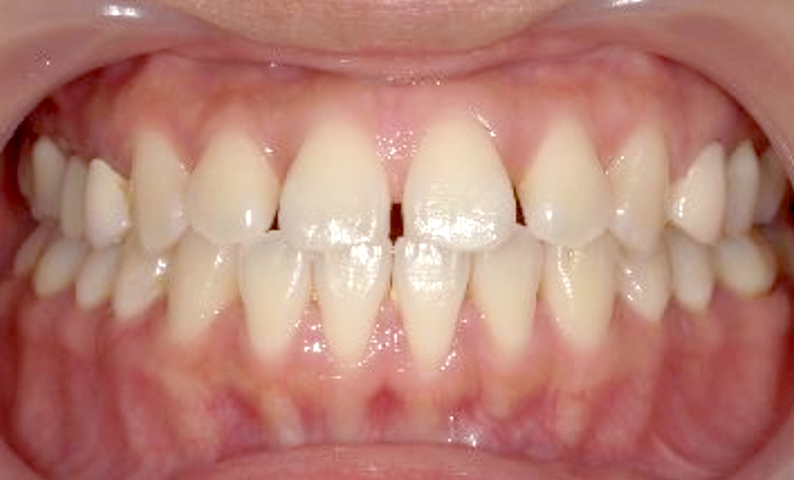

| 治療前 | 治療後 |

|---|---|

|